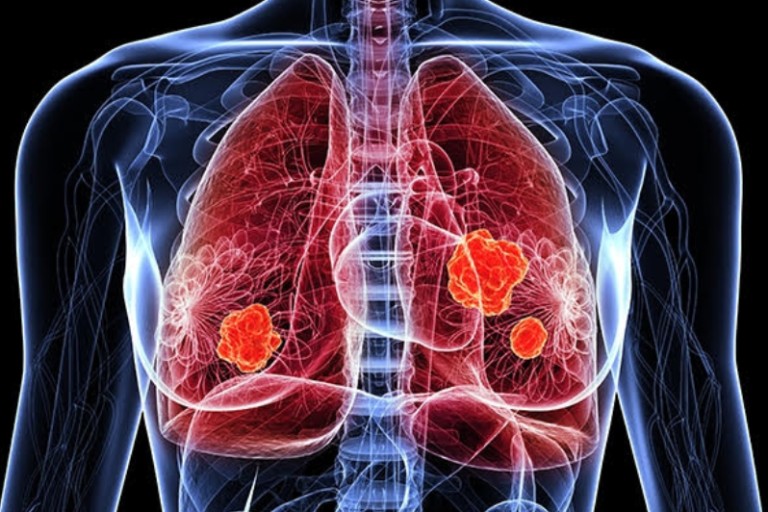

폐렴 치료방법

폐렴의 치료 방법은 원인에 따라 다르지만, 일반적으로 다음과 같은 치료가 진행됩니다:

폐렴은 조기에 치료하면 완치가 가능하지만, 늦으면 합병증이 발생할 수 있으므로 증상이 나타나면 즉시 의료기관을 방문하는 것이 중요합니다.